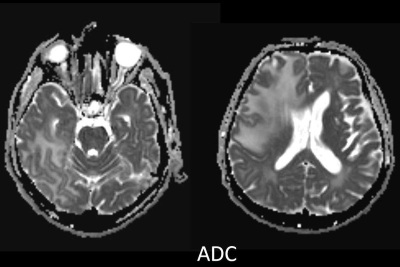

- B) ADC haritasında kolaylaşmış difüzyon (mavi ok).